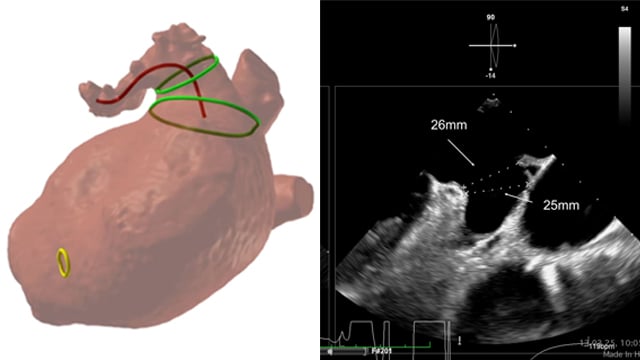

A simple maneuver to track the wire during a transseptal mitral valve-in-valve procedure

05 Nov 2025

Advancing a transcatheter heart valve through the septostomy can be tricky, with the wire sometimes prolapsing into the left atrium.

This step-by-step tutorial demonstrates a simple yet effective maneuver that allows smooth, controlled navigation from the right atrium to the mitral position, ensuring precise valve deployment.